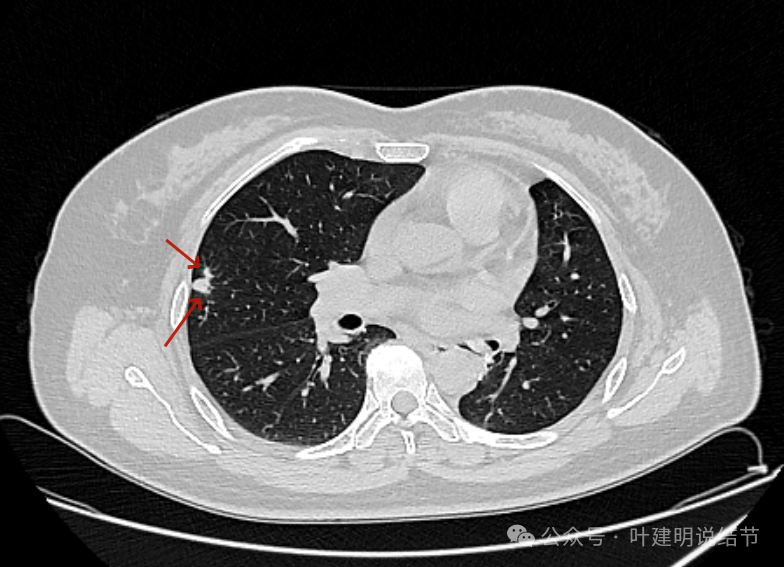

表面不平,血管走向病灶。部分边缘较为平直。

此层见病灶轮廓较清,有小血管进入,表面不平,有一定的膨胀感。部分边缘较为光滑。

胸膜间隙征存在,整体边缘显得较为光滑。